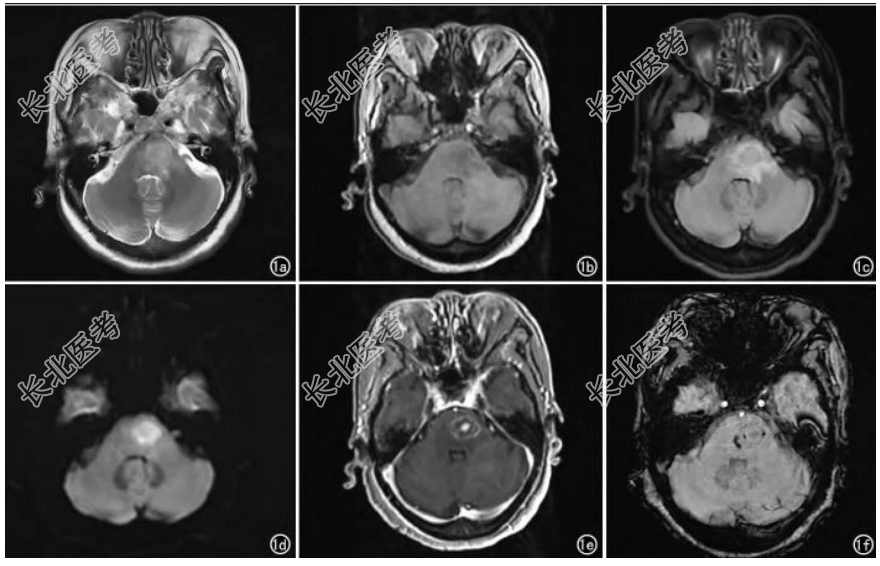

- [材料题] 患者,女,66岁,因“头痛1周,外院CT提示脑干占位1天”入院。患者一周前无明显诱因出现头痛不适,期间未行特殊治疗,1天前因头痛症状无好转,于外院行头颅CT检查发现脑干占位,为明确诊断遂来我院就诊。既往史及体格检查无特殊。脑脊液生化:氯132.8Mmol/l(110~130Mmol/l),葡萄糖2.26Mmol/l(2.5~4.4Mmol/l),尿总蛋白1866.9MG/L(150~450MG/L);脑脊液常规检查:潘氏试验阳性(1+);细胞因子七项:白细胞介素-6 36.98PG/ML(0.00~9.10PG/ML)。头颅MRI平扫+增强:脑内多发斑片状T1WI低信号和T2WI高信号,T2-FLaIR呈高信号,较大病灶位于脑桥,dWI序列呈环状高信号,对应adC图呈低信号,磁敏感加权成像病灶内部及周围见线状及点状低信号,大小约1.4cm×1.1cm×2.1cm,增强扫描呈环状强化,其内见结节状明显强化(图1)。脑脊液病原微生物宏基因组检测(dNa+RNa):狒狒巴拉姆希阿米巴,检出序列数12036,相对丰度99.19%,置信度高。

- 简答题3、从该患者的检查结果看,狒狒巴拉姆希阿米巴脑炎的MRI影像学表现有哪些?